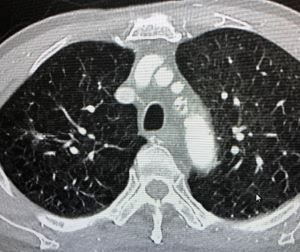

Initial Diagnostic Testing